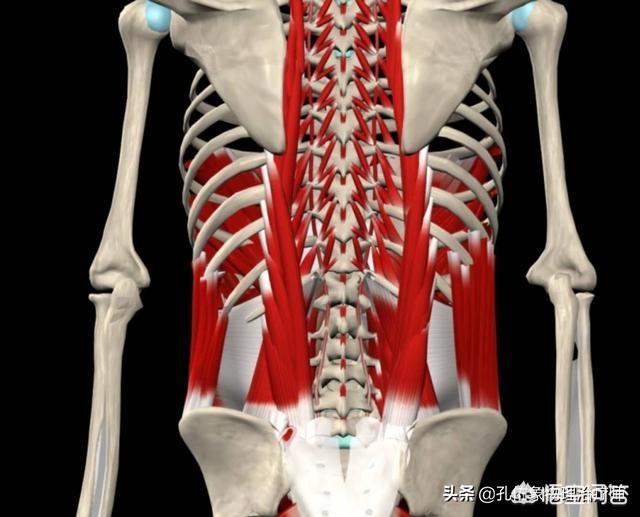

tension musculaire lombaireIl existe de nombreux muscles dans le dos lombaire, tels que le muscle sacro-épineux, le plus puissant, qui est le muscle clé pour maintenir notre taille en arrière et en position verticale, et le processus transversal des vertèbres qui a des épines transversales, qui sont les muscles semispinalis, multifidus et piriforme, et les muscles courts plus profonds tels que les muscles intertransversaires et interépineux ; quelle que soit la position de votre taille, les muscles lombaires sont en état de contraction et doivent résister à la gravité, ce qui entraînera une fatigue des muscles lombaires. Quelle que soit votre posture, les muscles du bas du dos sont en état de contraction et doivent résister à la gravité, ce qui entraîne une fatigue des muscles lombaires.

Le claquage musculaire lombaire est l'un des troubles chroniques des tissus mous de la région lombaire, et il existe plusieurs autres membres de cette famille, tels que le claquage fascial et le claquage ligamentaire. Le claquage musculaire lombaire, qui est une inflammation chronique des muscles lombaires et de leurs points d'attache, le fascia et le périoste, est une cause fréquente de lombalgie chez la plupart des gens.

Dans la vie, si nous sommes souvent occupés à des travaux ou à des sports en position debout ou avec des charges lombaires, nous sommes souvent sédentaires et nous manquons d'exercice.L'accumulation répétée de blessures mineures dans la région lombaire entraîne des changements pathologiques au niveau des points d'attache des muscles lombaires, du périoste, des ligaments et d'autres tissus, qui irritent ou compriment les terminaisons nerveuses et provoquent des symptômes de lombalgie, connus sous le nom de claquage musculaire lombaire.